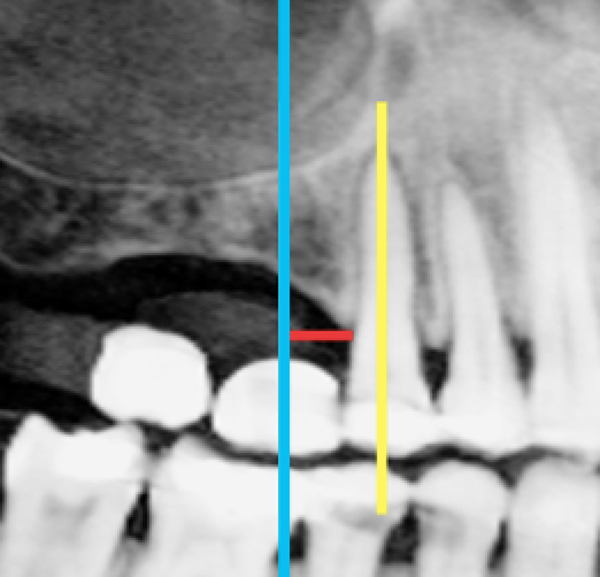

Măsurătorile din scanarea CBCT au fost înregistrate pe secțiunea transversală. O linie dreaptă perpendiculară pe o tangentă la creastă a fost extinsă până la podeaua sinusului maxilar. S-a măsurat lungimea liniei și s-a notat ca „înălțimea crestei CBCT” (fig. 1, 2). Măsurătorile periapicale ale aceleiași zone au fost înregistrate prin extinderea unei linii drepte paralele cu axul lung al dintelui natural sau implantului adiacent, de la creasta alveolară până la podeaua sinusului maxilar. Lungimea liniei a fost măsurată și înregistrată ca „înălțimea crestei PA” (fig. 3).

În trecut, pentru a obține radiografii PA clinicienii foloseau adesea tehnica bisectoare în care raza centrală era direcționată către o linie care bisectează axul lung atât al dintelui cât și al suportului de film. În prezent, este populară tehnica de paralelizare deoarece oferă în mod inerent mai puțină distorsiune și o precizie mai mare în măsurare decât tehnica bisectoare.13 Acest lucru este esențial în special în domeniul endodonției pentru determinarea lungimii rădăcinii. Totuși, această caracteristică nu se aplică în stomatologia implantară, întrucât există o absență a identificatorilor cheie sau a punctelor de măsurare, cum ar fi muchia incizală sau vârful rădăcinii (fig. 4, 5), ceea ce face dificilă măsurarea înălțimii crestei și eliminarea oricărei repetabilități în măsurători, intervenind astfel erori.

În mod similar, atunci când se extrage un dinte, operatorul poate introduce senzorul de raze X în mod eronat și, adesea, dinții restanți și creasta alveolară pot avea un ax longitudinal diferit (fig. 6-8), împiedicând operatorul să atingă adevăratul paralelism pentru o acuratețe a utilizării instrumentului de măsurare.